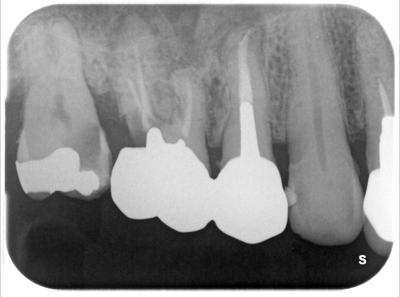

HOME > ブログ 一覧 > インプラント治療 2021.12.13インプラント治療 右上部にサイナスリフト(ソケットリフト)を伴うインプラント治療。 術前。 右上765大きな虫歯、65は歯根破折起こしており保存不可能と判断、抜歯。 使用インプラントはASTRA TX、EV(スゥエーデン) 2次オペ終了時。 年内に765部にプロヴィジョナル装着予定。 この部位以外にも全顎的包括診療行っている。 ここまで治療期間約7ヶ月。 インプラント埋入処置の所要時間は30分程度です。 Recent Entries アライナー矯正(インビザライン、シュアスマイル)費用を2023年 1月から改訂させていただきます(01/09) 本年もよろしくお願いいたします(01/02) 年始の診療について(01/01) 新しいWEBへ移行、年末年始の診療のお知らせ(12/29) ダラダラ根管治療行っても治らないという事(12/21) Category その他の治療(126) インビザライン・矯正(52) インプラント治療(216) ホワイトニング(47) メインテナンス(21) 包括診療(95) 医院からのお知らせ(249) 審美治療(128) 日々雑感(283) 根管治療(100) 歯周病治療(90) 矯正(73) 補綴治療(45) 補綴治療カテゴリを追加(1) 診療全般(44) Archive 2023年1月(3) 2022年12月(6) 2022年11月(14) 2022年10月(6) 2022年9月(8) 2022年8月(7) 2022年7月(13) 2022年6月(8) 2022年5月(7) 2022年4月(7) 2022年3月(6) 2022年2月(7)